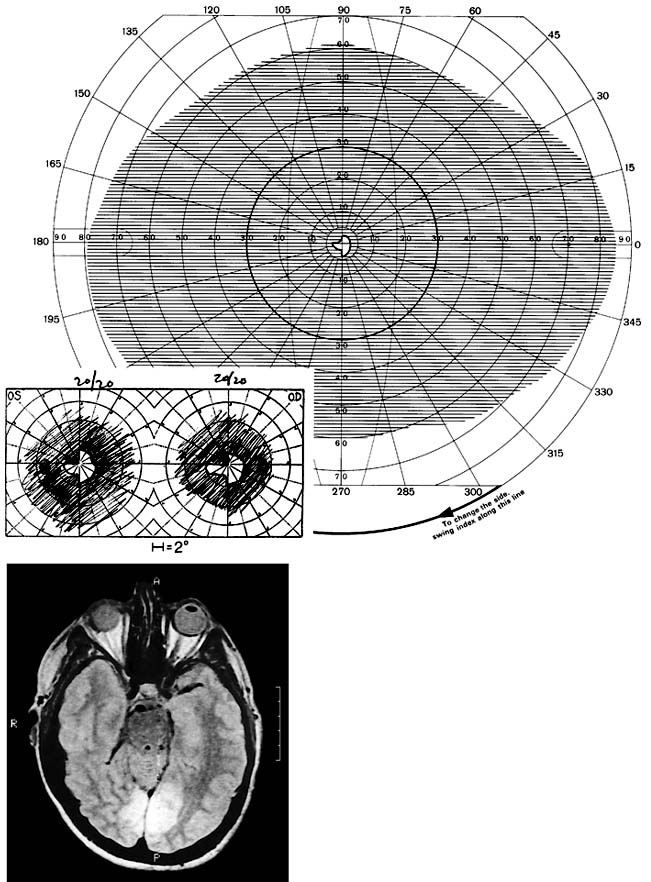

Figure 14-5

Figure 14-5: Bilateral occipital infarcts with bilateral macular sparing. Top: Tangent screen and superimposed Goldmann visual fields of both eyes showing bilateral homonymous hemianopia with macular sparing, greater in the right hemifield. Bottom: Axial MRI showing sparing of occipital poles. (Reproduced, with permission, from Horton JC, Hoyt WF: The representation of the visual field in human striate cortex. A revision of the classic Holmes map. Arch Ophthalmol 1991;109:816.)